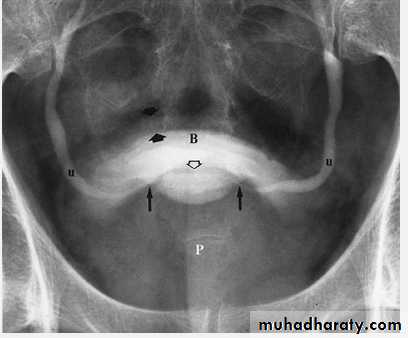

Benign Prostatic Hypertrophy. A radiograph from an excretory urogram shows marked uplifting of the bladder base because of massive enlargement of the prostate (P). The trigone (open arrow) and ureteral orifices (black arrows) are markedly elevated, resulting in a J-shaped appearance to the distal ureters (u). The bladder wall is thickened (between black arrowheads), and the bladder (B) mucosal pattern is prominent.